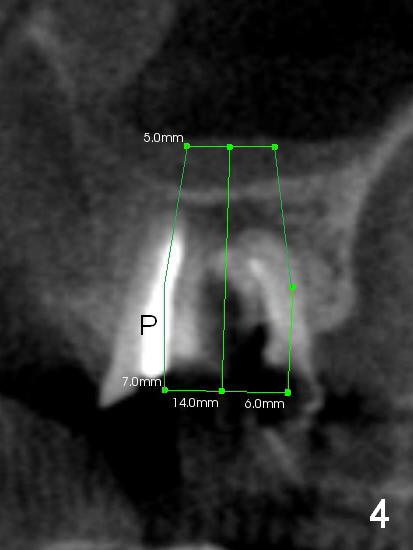

The tooth #15 of a 62-year-old man (CY) has been fractured for 4 years (Fig.1).  The 3 roots (MB, DB and P) appear to be approximated each other (Fig.1,3,4) so that when the tooth is extracted (using a surgical handpiece for sectioning), the socket should be single and large.  Treat the socket with Clindamycin.  If the socket proves to be flat on the top, the thickness of the sinus floor is approximately 2 mm.  If the bone is not so tough, use osteotomes to do sinus lift; otherwise use drills.  The depth of osteotomy should be tightly monitored.

PA shows that the depth of the osteotomy is approximately 17 mm (Fig.2), whereas CT 14 mm (Fig.3,4).  Intraop measurement will determine the depth.